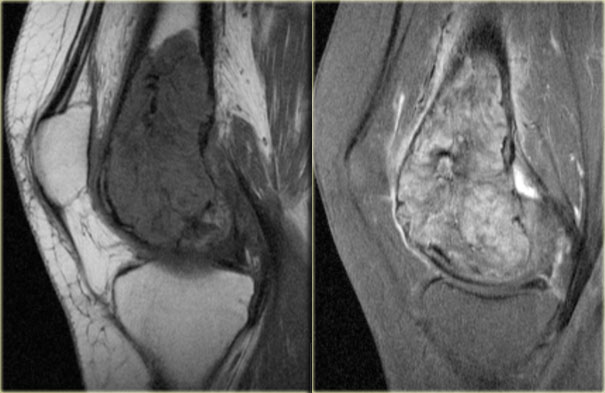

Giant cell tumor (2) continued

MR-images of the same patient.

Sagittal T1-weighted TSE images before and after Gd.

The tumor extends to the subchondral bone plate with endosteal cortical involvement.

There is inhomogeneous enhancement.

On T2-weighted image, the tumor has a remarkable low SI, which is commonly seen in GCT.

There is surrounding edema with high SI.